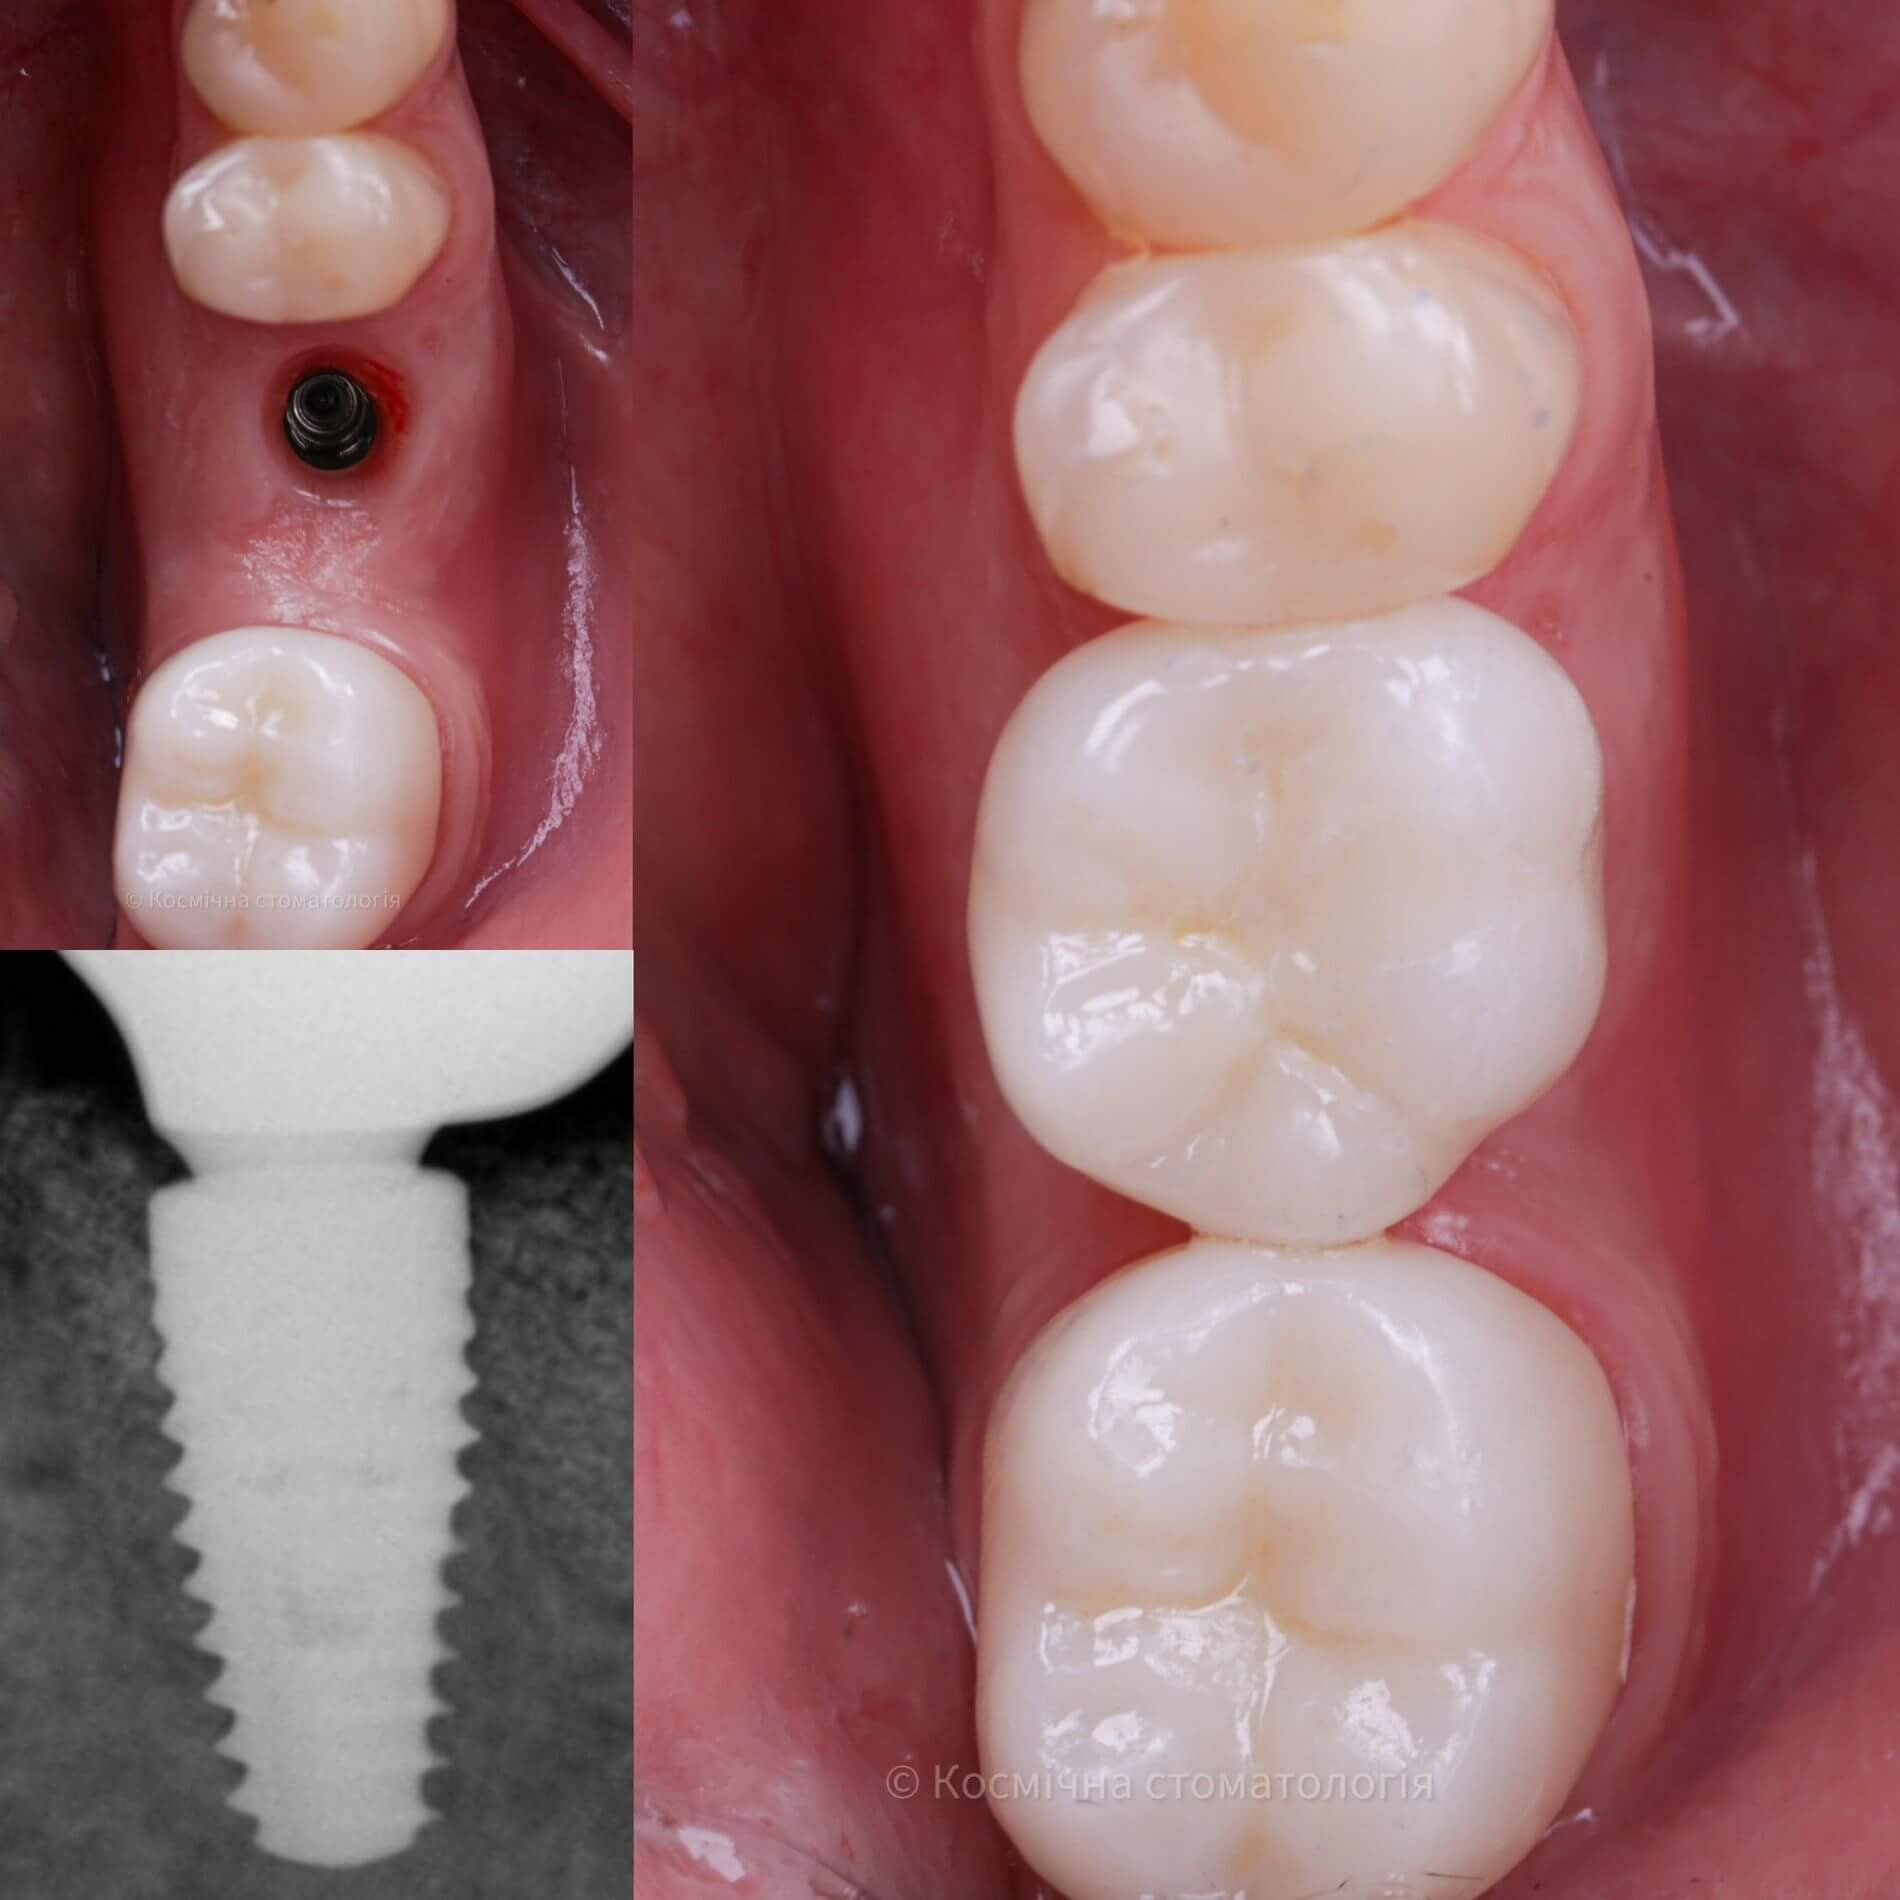

Імплантація - це метод вживлення імплантату (штучного кореня) у верхню або нижню щелепу.Такий штучний корінь виготовляється з спеціального сплаву, що надійно вживлюється в кістку та стає надійною опорою, на яку встановлюється коронка.

- Двоетапна імплантація відбувається в два послідовні етапи: спочатку здійснюється встановлення імпланту та витримується термін його повної остеоінтеграції (2-4 місяці, в залежності від щелепи), після чого встановлюється коронка;

Залежить від щелепи: остеоінтеграція на верхній щелепі відбувається за 3-4 місяці, на нижній - за 2-3. Отут ти точно здивувався. Так, на різних щелепах різні терміни приживання, бо кістка верхньої та нижньої щелеп відрізняються за своєю структурою.

- кріплення абатменту та коронки;